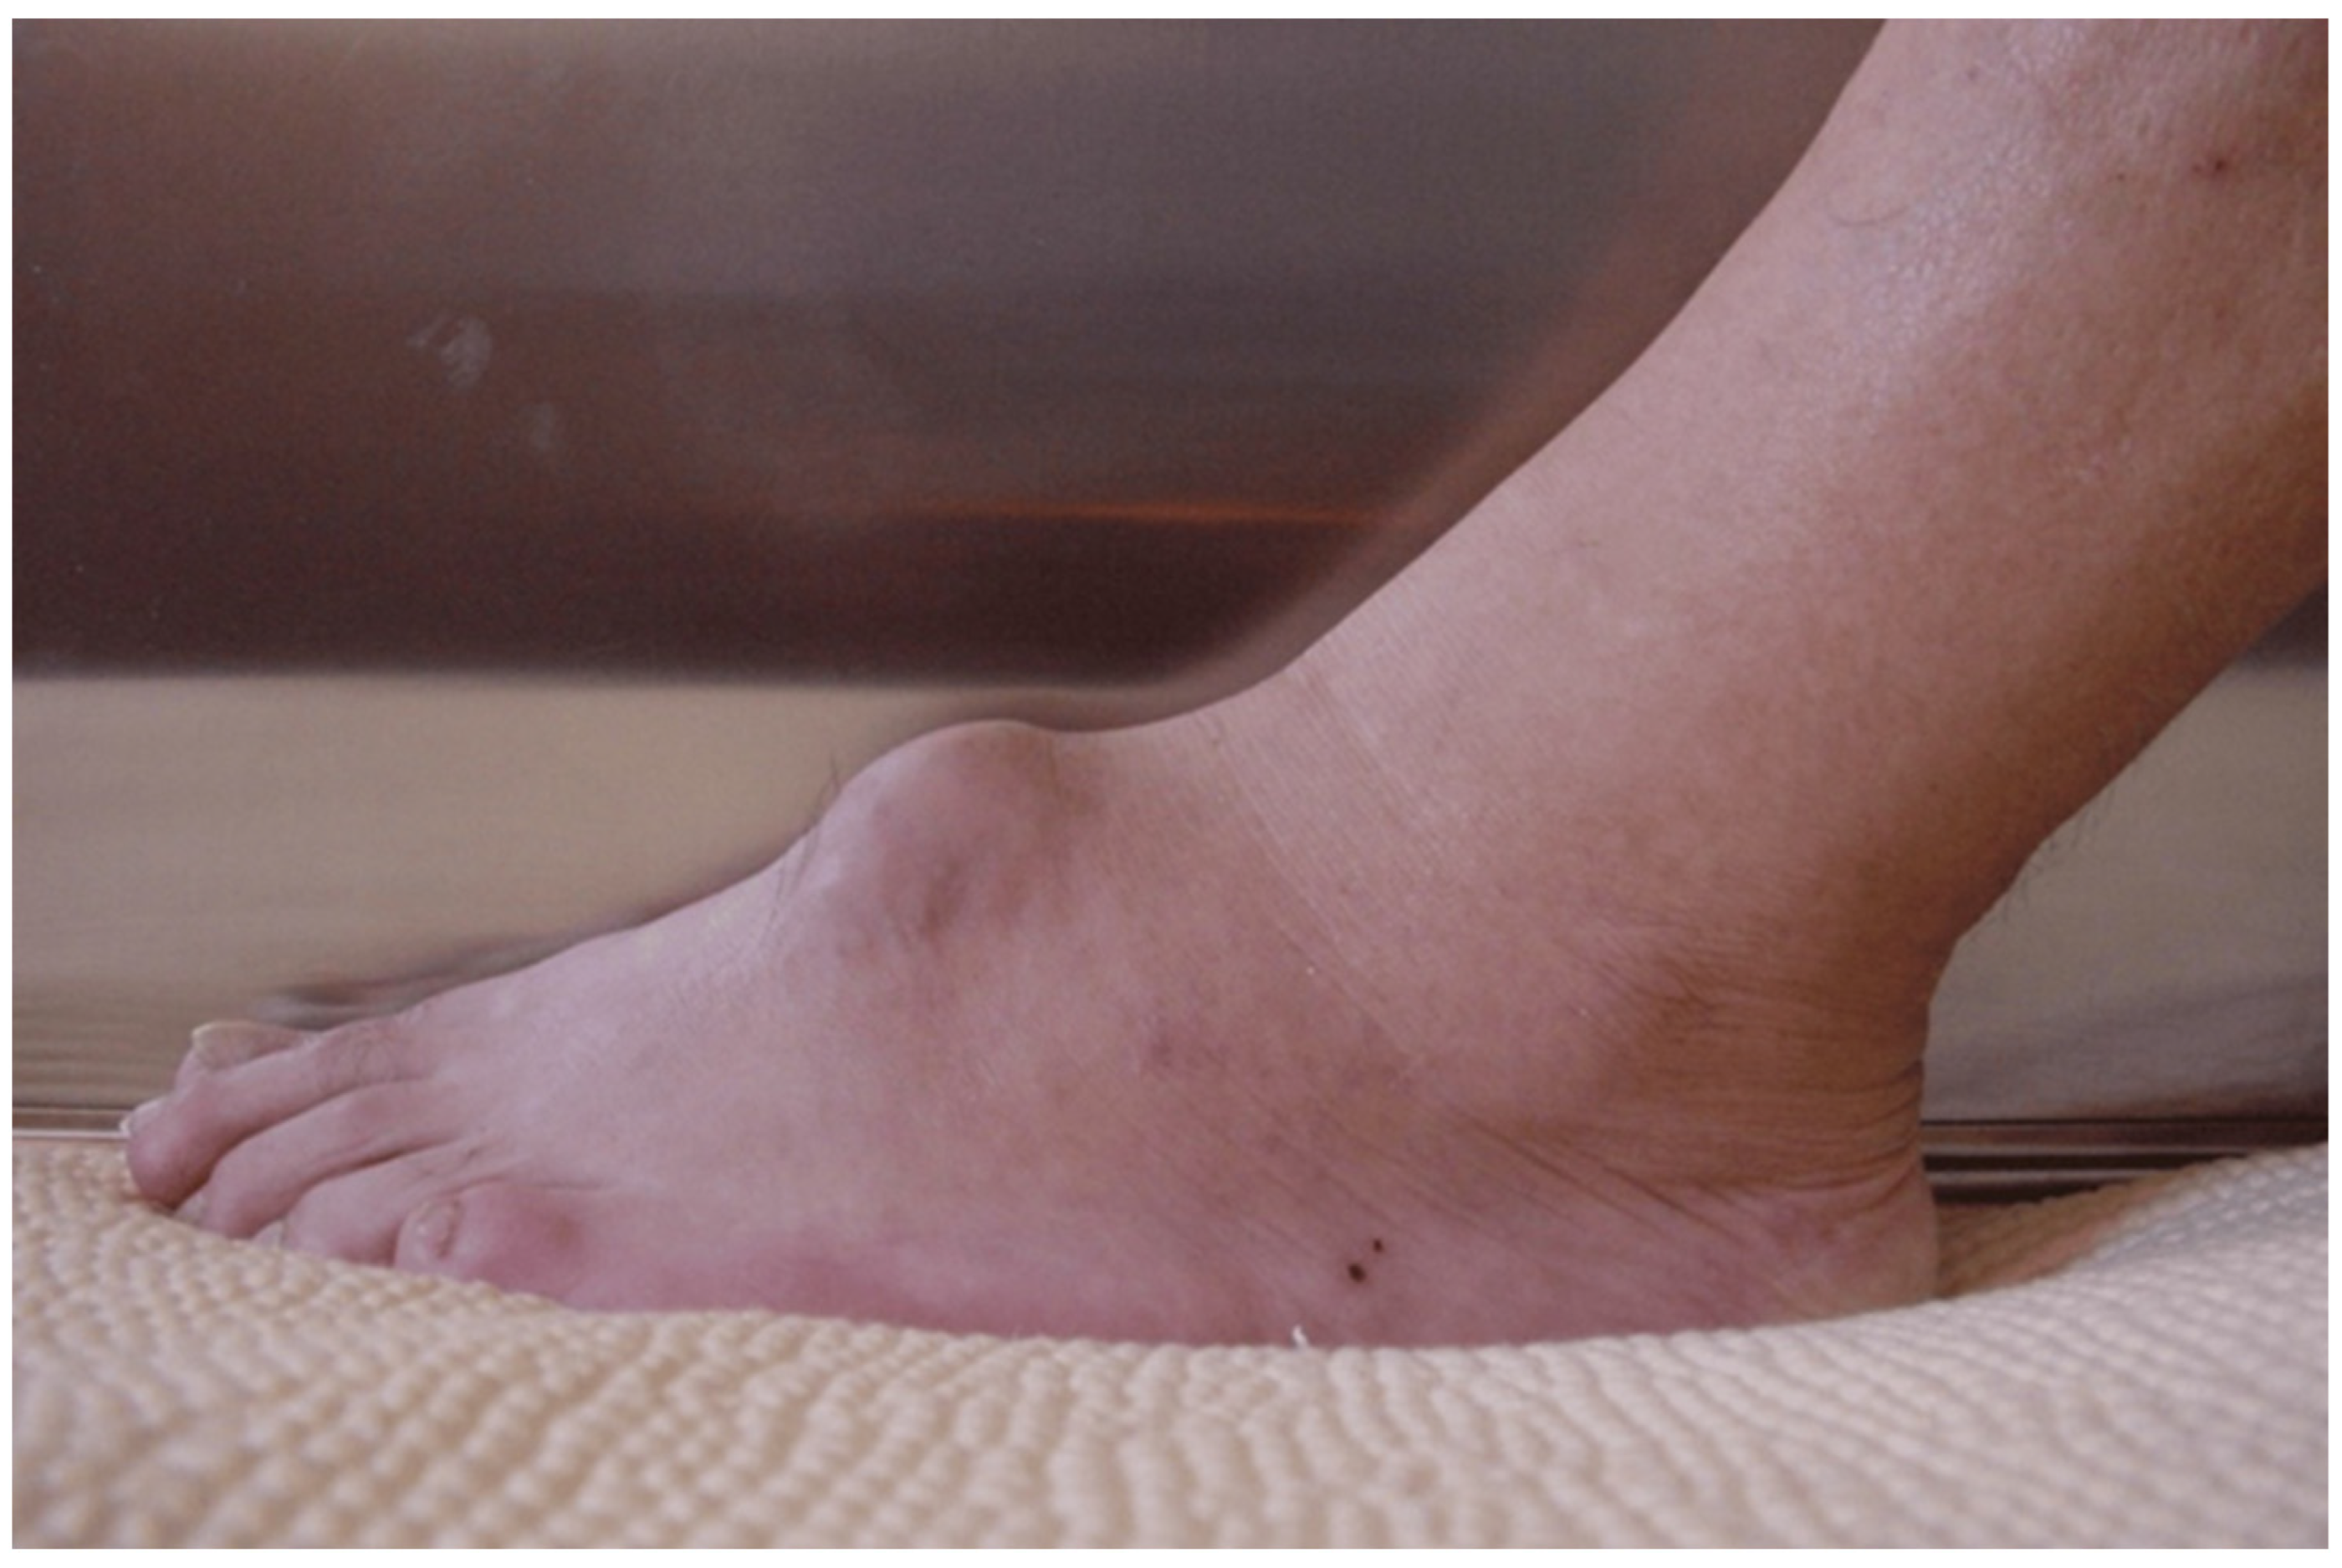

3. Clinical Presentation